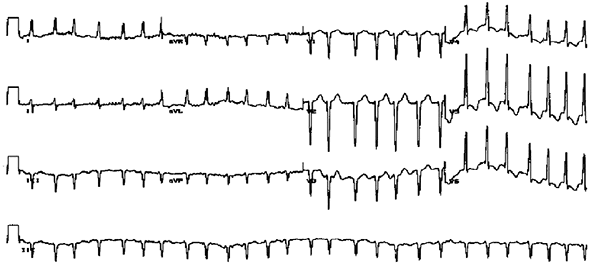

Иллюстрация к книге — Хрупкий мозг. Инсульту не быть? [img_39.jpg]

Типичная электрокардиограмма сердца при мерцательной аритмии

Значимой проблемой, угрожающей здоровью многих больных, является возрастание частоты нарушения ритма сердца в виде мерцательной аритмии или, по-другому, фибрилляции предсердий. Такое нарушение характеризуется внезапными приступами ускоренного сердцебиения, ощущениями, что «сердце вот- вот выпрыгнет из груди». Иногда больные описывают ощущения остановки сердца на несколько секунд, после чего оно начинает биться с удвоенной скоростью. Всё это сопровождается сильной слабостью. Дело в том, что две камеры сердца — предсердия — перестают нормально и синхронно сокращаться. Из-за этого уменьшается количество крови, поступающей в другие камеры сердца — желудочки, которые обеспечивают кровоток в органах и системах человеческого организма. Как и при других заболеваниях, риск развития мерцательной аритмии увеличивается с возрастом человека, особенно после 40-летней отметки. По некоторым прогнозам, число больных с нарушением ритма сердца удвоится в ближайшее время дважды — к 2030 и 2050 годам.

Помимо «проблем с сердцем» мерцательная аритмия является очень серьёзным фактором риска развития инсульта, и вот почему: хаотичные сокращения стенок сердца приводят к тому, что образуются зоны застоя крови, где складываются условия для образования тромбов, которые могут разноситься по сосудам человека, попадая в том числе в головной мозг, вызывая развитие инсульта. Было установлено, что у больных мерцательной аритмией инсульт развивается от 5 до 17 раз чаще, чем у пациентов с нормальным ритмом. Инсульт, возникающий при попадании тромбов из сердца в сосуды головного мозга, получил название «кардиоэмболический» и по частоте уверенно занимает второе место после атеротромботического типа, о котором мы уже упоминали. Кардиоэмболический инсульт, обусловленный мерцательной аритмией, — одно из самых убийственных заболеваний. Он заканчивается смертью или значительной инвалидизацией большинства пациентов.